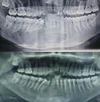

Mezun olduğu yıl İstanbul Üniversitesi Diş Hekimliği Fakültesi Ağız, Diş ve Çene Cerrahisi Anabilim Dalı’nda doktora eğitimine kabul edilmiştir. 2018 yılında ‘Ön Açık Kapanış Olgularında Uygulanan Le Fort I Osteotomisinin Stabilizasyonunun Farklı Plak Tasarımına ve Ameliyat tekniklerine Göre Sonlu Eleman Analiz Yöntemiyle İncelenmesi’ konulu tezini sunarak doktorasını tamamlamış ve ‘Bilim Doktoru’ ünvanı almıştır.